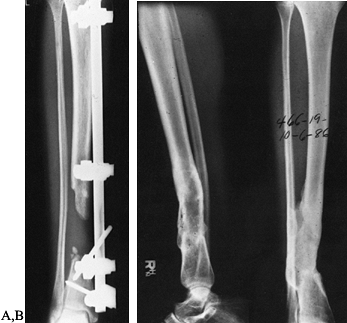

Figure 133.12. Anteroposterior (A) and lateral (B)

radiographs of the tibia and fibula in a 21-year-old man who had a previous posterior bone graft and now shows the presence of a large sequestrum. Lateral film (C) shows debridement of the infection and sequestra. Lateral film (D) taken 10 months after a local flap was performed and an autogenous cancellous bone graft was performed. |

![]() |

Figure 133.13. A: Anteroposterior radiograph of a 34-year-old woman with approximately a 6 cm defect. B:

Anteroposterior and lateral films taken 1 year following performance of an autogenous cancellous bone graft to fill dead space caused by bony defects. |

Figure 133.15. A:

Lateral radiograph of the tibia and fibula in a 37-year-old woman with

loss of the tibia following an infection that developed after the

patient sustained a type III open fracture. B: Anteroposterior photograph shows the soft-tissue and bone loss and exposed tibial shaft. C: Photograph taken at the time of autogenous cancellous bone grafting of the dead space. D,E: Anteroposterior and lateral radiographs, taken after the grafts had consolidated, show healing of the fracture. F:

Lateral photograph, taken 3 years after the procedure, shows knee

flexion and the appearance of the leg. The patient has been free of

infection.